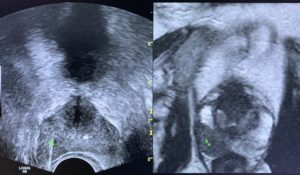

Biopsia próstata com fusão